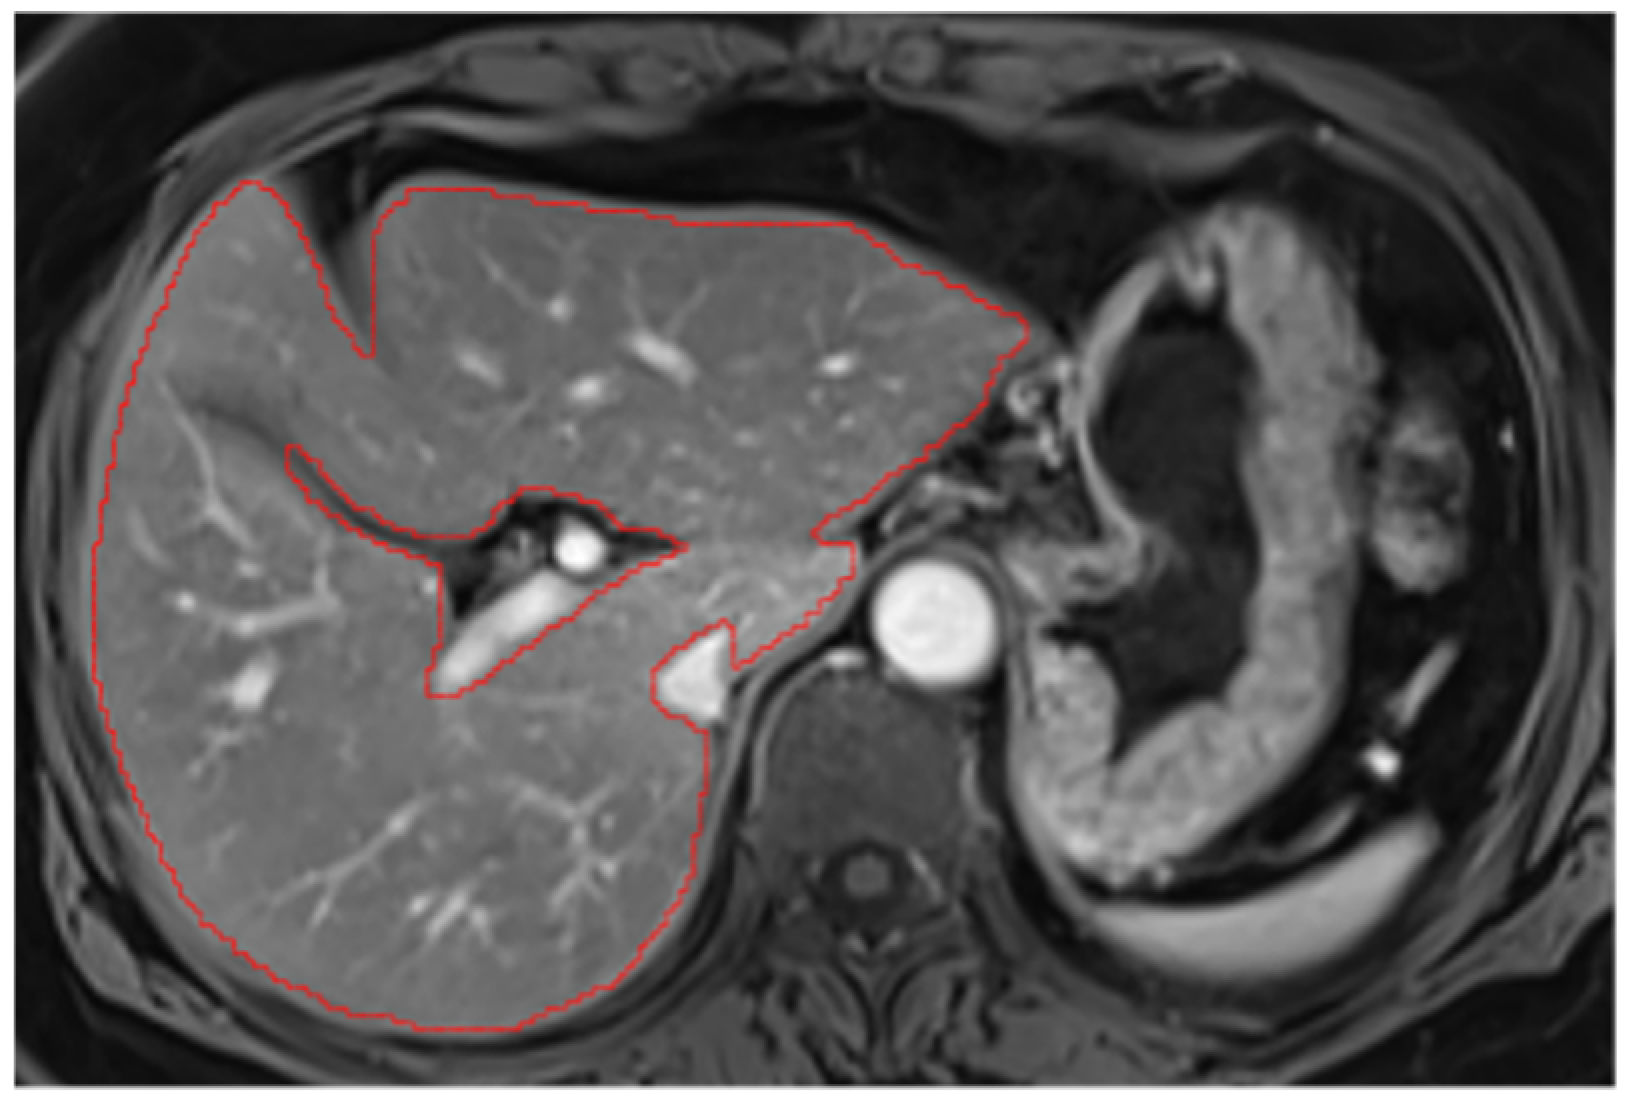

Appendix A.3. Vascular Segmentation